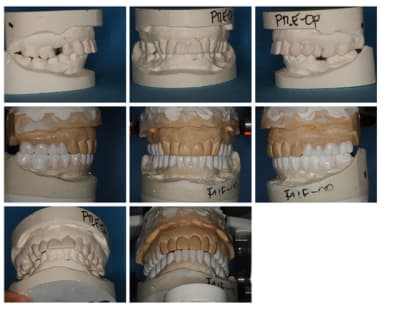

Suite du p'tit cas de ré-hab.

Cirage (wax-up en français ;-))

Gain en vertical et en AP (antéro-postérieur)

Disparition de la Cl-2 par callage postérieur et repositionnement mandibulaire.

Prochaine étape, placer cela en bouche (provisoires).

A suivre...(le cas est en cours, faut être patient)

Regarde bien le cirage/wax-up vue de côté.

J'ai ouvert plus en postérieur, qu'en antérieur, et plus d'un côté que de l'autre, et modifié la position antéro-postérieure. J'ai travaillé sur plusieurs axes (d'où l'inutilité de bouger la tige de l'articulateur).

Regarde bien le wax-up.